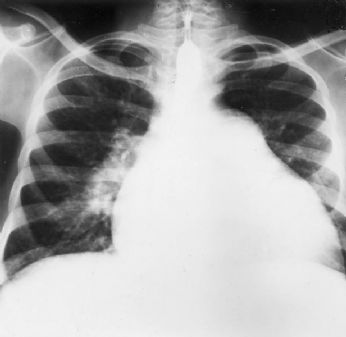

Strana tosse...quella che avevo durante la febbre mi è passata... ma sto gusto di sangue che ho adesso, sto catarro venato di porpora... mmm...non mi convince... cof cof... affanculo... fumare meno...